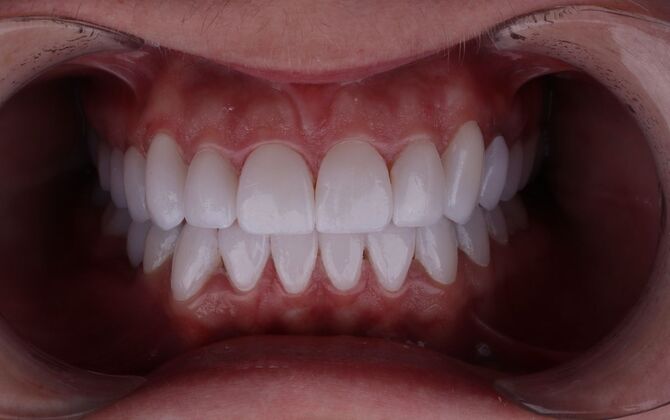

Porcelain Veneers: Michelle

Description

A smile is a very important part of one's appearance and is often the first thing people notice. Every person has a different color of teeth, and many have a different shape. Luckily there is a solution to improve your smile: Veneers!